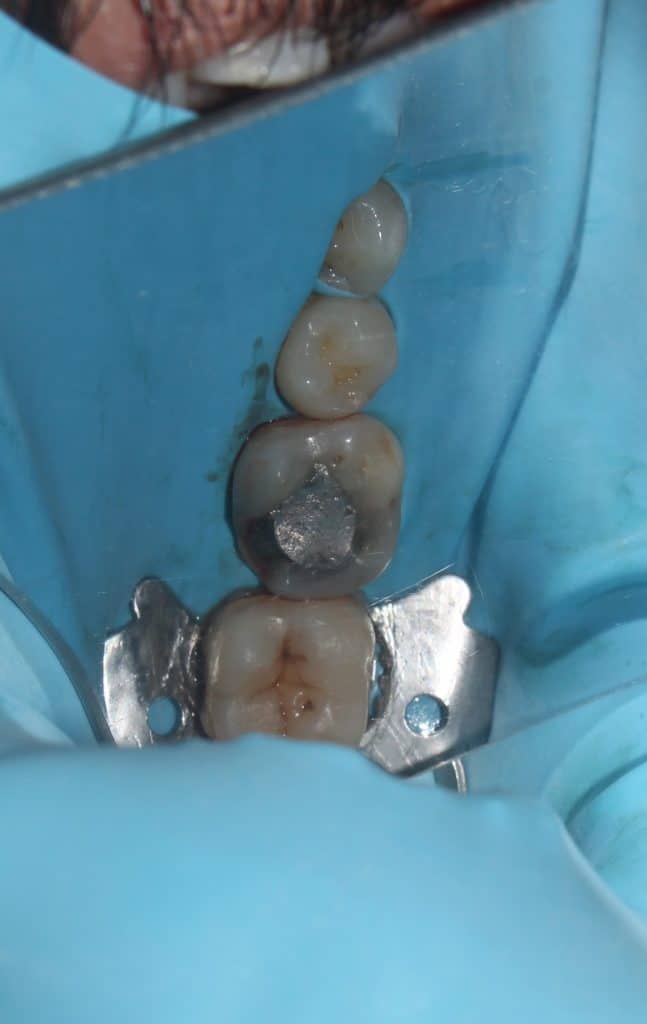

Replacement of old amalgum with a fracture of the distolingual cuspal wall.

Initial presentation showing fracture of the disto lingual cusp of old amalgum restoration.